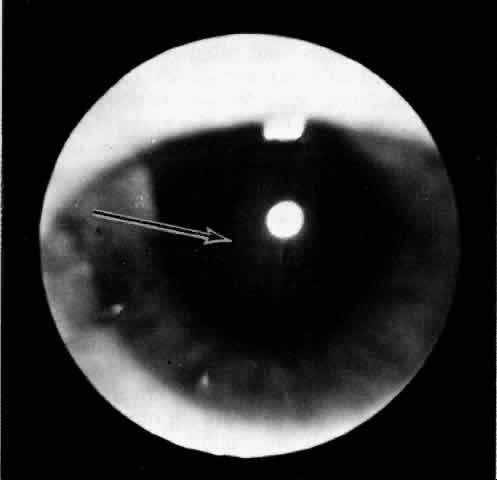

Fig. 2. The ora serrata is visible in the pupillary space due to a ciliochoroidal effusion that developed after retinal detachment surgery in an aphakic eye. The arrow indicates the ora bay. (Courtesy of Retina Service, Wills Eye Hospital, Philadelphia)

The presence of certain clinical characteristics may assist in the diagnosis of a ciliochoroidal effusion (Table 1). One clinical feature is choroidal edema. Choroidal edema may resemble a retinal detachment to a hasty observer; however, darkness of the uvea, lack of tremulousness, and normal retinal vessels indicate a probable uveal process (Fig. 1). The effusion may extend under the pars plana, allowing visualization of the ora serrata without scleral depression (Fig. 2).9 As shown in Figure 2, the surface of the elevation is convex and smooth, with a solid appearance and a homogeneous grayish color. A shallow anterior chamber and a low intraocular pressure may also suggest the diagnosis. Myopia in the presence of anterior displacement of the lens-iris diaphragm may be another diagnostic clue.10,11

Fig. 5. Flat ciliochoroidal effusion. The ora serrata is visible without scleral depression in a patient with Schepens-Brockhurst syndrome. The arrow indicates the ora bay.